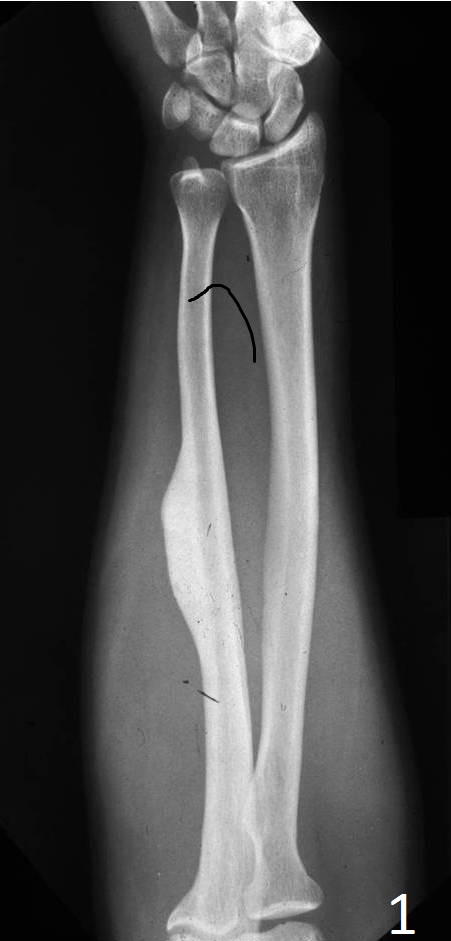

Plain x-ray

• Sharply defined, radiopaque smooth, homogeneous bone protruding from the surface of a bone

• Almost appears as a localized thickening of the bone

Fig. 1. AP xray of forearm show a superficial bone lesion in the shaft of the ulna consistent with an osteoma.